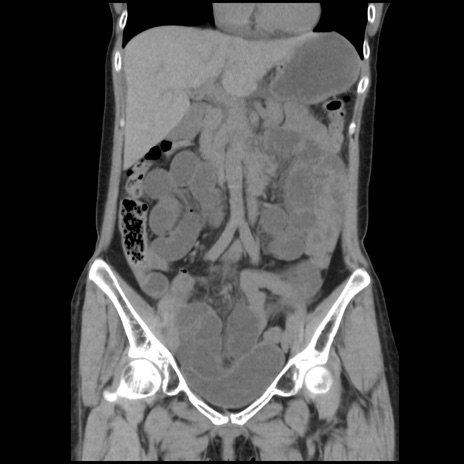

症例32(冠状断像)

【症例】40歳代 女性

【主訴】上腹部痛、嘔気・嘔吐

【現病歴】約9時間前頃から急に上腹部痛、嘔気、嘔吐が出現。改善しないため救急要請。

【既往歴】子宮頚癌(広汎子宮全摘術、放射線療法)、腸閉塞

【身体所見】腹部:平坦、軟、腸雑音亢進、上腹部を中心に腹部全体に圧痛あり。

【データ】WBC 8400、CRP 0.03